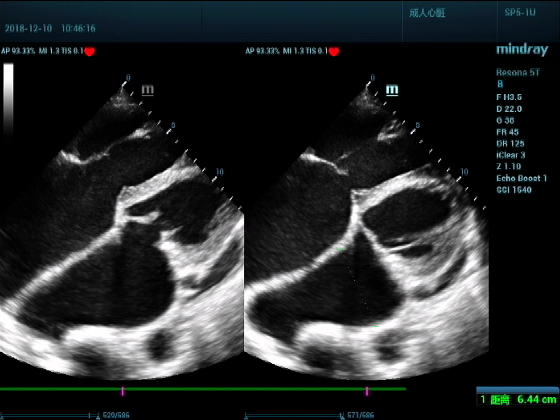

男,81岁,全身浮肿来住院

超声可见:左房,右房,右室明显增大,主肺动脉及右肺动脉增宽,二尖瓣中度反流,三尖瓣重度反流,肺动脉轻度高压,心律不齐

心包积液盆腔积液。淤血性肝增大,肝静脉增宽。(右心衰声像改变)